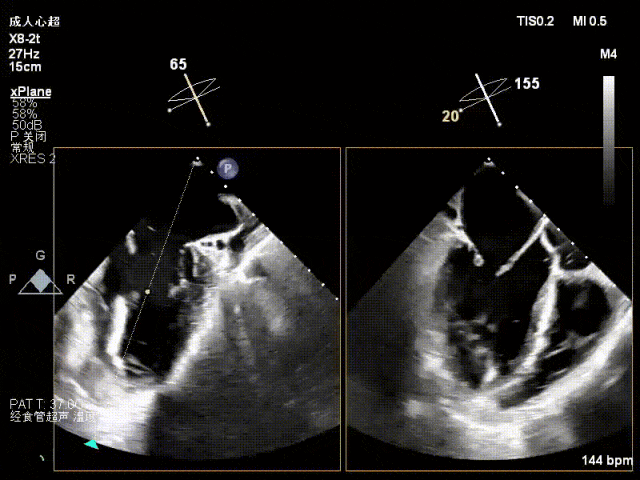

术前心超

功能性MR,P3脱垂,新分型:BAA型

反流主要集中于3区,MR中度,VC:2×4mm

A2:24mm,P2:16mm,AP:38mm,MVA约4.6cm²

术中超声要点